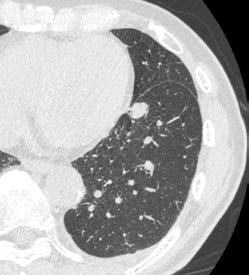

Aquilion ONE / INSIGHT Editionは、ハードウエア系の一新で0.24秒のガントリ回転速度など基本性能を向上させ、AI技術によって開発された超解像画像再構成技術「Precise IQ Engine(PIQE)」、モーションアーチファクト低減技術「CLEAR Motion」などを搭載したフラッグシップCTである。画像の評価を佐藤部長は、「PIQEによる再構成は予想以上にノイズが低減されており、従来と同等の線量でも大きく画質が向上しています。血管系の精度向上はもちろんですが、肝実質や膵実質など実質臓器についてもノイズの低減で読影がしやすくなっています。読影では消化管も見ていますが、解像度の向上とPIQEによってクリアに描出されて、管腔構造の連続性が認識しやすく、壁構造のコントラストが向上して粘膜変化をとらえやすくなっており評価が容易になっていると感じます」と述べる。PIQEは肺野を除く全例で適用されている。肝細胞がんの症例(図1)では、3か月前にIVR-CTの80列で撮影した画像に比べて、ほぼ同条件で撮ったAquilion ONE / INSIGHT Editionの画像では早期濃染を示す小病変がより明瞭に描出されている。また、胃潰瘍の症例では、通常の造影検査で粘膜の欠損や粘膜下の浮腫が明瞭に描出されていた。佐藤部長は、「従来は小さい消化管病変は疑いを指摘するにとどまっていましたが、より確信を持って診断できます」と述べる。

図1 肝細胞がん a

a:Aquilion PRIME(AIDR 3D

b:Aquilion ONE / INSIGHT Edition(PIQE)